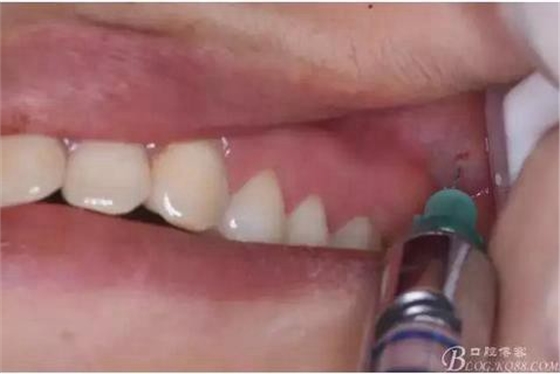

圖2.行左側(cè)28前庭溝浸潤(rùn)麻醉,注意應(yīng)半閉嘴進(jìn)行前庭溝進(jìn)針

圖3. 腭側(cè)在28區(qū)域進(jìn)行浸潤(rùn)麻醉